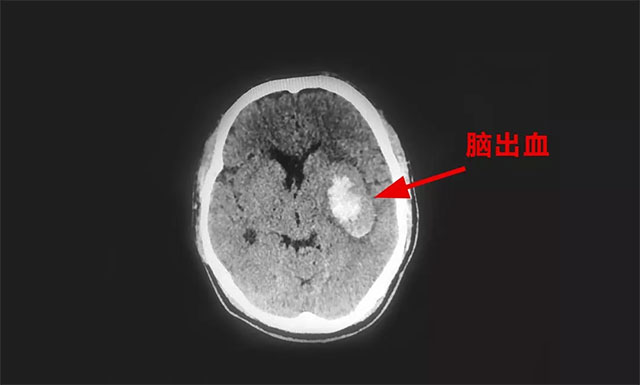

▲ 脑出血部位示意图

经头颅CT检查,汪先生被诊断为左侧基底节区出血。除了右侧肢体瘫痪,患者还出现了精神躁动、言语不清的情况,病情快速加重。

▲ 患者左侧基底节区二次出血伴水肿带环绕